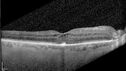

Paclitaxel induced cystoid macular edema - reversed when chemo stopped25 views74 year old retired physician About 2-3 weeks ago there was gradual vision loss in the right eye. The patient was seen by an ophthalmologist who saw macular swelling and injected vabysmo. He has been on chemotherapy (Carbiplatin and Carboxytaxol for 2 cancers - advanced prostrate diagnosed 2019 - has had brain surgery AND squamous lung cancers treated with radiation)

Medical Hx: Prostate cancer (Onset: 2018). Pulmonary and bone cancer metastatic. Brain cancer metastasized from prostate cancer.

Surgical Hx: Right frontal & Frontoparietal Craniotomy (Onset: 2024). Appendectomy. Hemorrhoidectomy. Herniorrhaphy. Prostate. Systemic Meds: Chemotherapy. Radiation. Eligard Every 3 Months 22.5 MG per 0.375 ML Prefilled Syringe. MIRALAX prn. Tums Freshers 500 MG Chewable Tablet. Vitamin D. XGEVA.

VA OD: Dcc20/125+1

VA OS: Dcc20/125-2

TP: OD:12 OS:15Aug 17, 2025